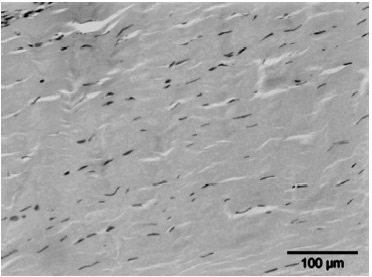

2) Tissue regeneration

Een tweede hypothese is dat ESWT een positief effect heeft op weefselregeneratie door:

- De toename van neovascularisatie in de pees-bot overgang.

- Het opwekken van groeifactoren zoals vasculo-endothelial growth factor (vegf).

- Het stimuleren van de collageenproductie en het afvoeren van beschadigd collageen, wat resulteert in een verhoogde matrix-turnover.

- Het beïnvloeden van stamcelmigratie en -proliferatie via mechanotransductie.

- De stijging in de celpermeabiliteit. De stimulatie van de celdeling.